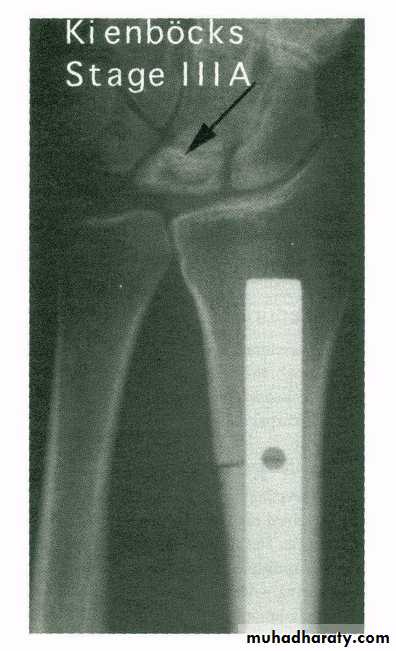

Rx : if function affected osteotomyKienbock disease

= crushing osteochondritis of lunate

It is AVN of lunateCause : unknown

May be : relatively short ulnaCF: wrist pain & weak grip

XR: bone densitycollapse

OA

Rx : splintage

shortening of radius

arthrodesis